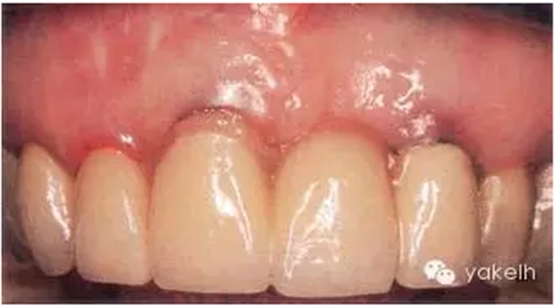

患者先天缺失側(cè)切牙,同時(shí)由于外傷UR1缺失。UR1種植修復(fù)。該種植冠大約有2mm 的牙齦退縮,與UL1相比,該修復(fù)冠較長(圖.8A)。這是由于種植體植入位置過深而導(dǎo)致的(圖.8B)。

圖.8 種植體植入過深,引起牙齦退縮以及修復(fù)冠過長。